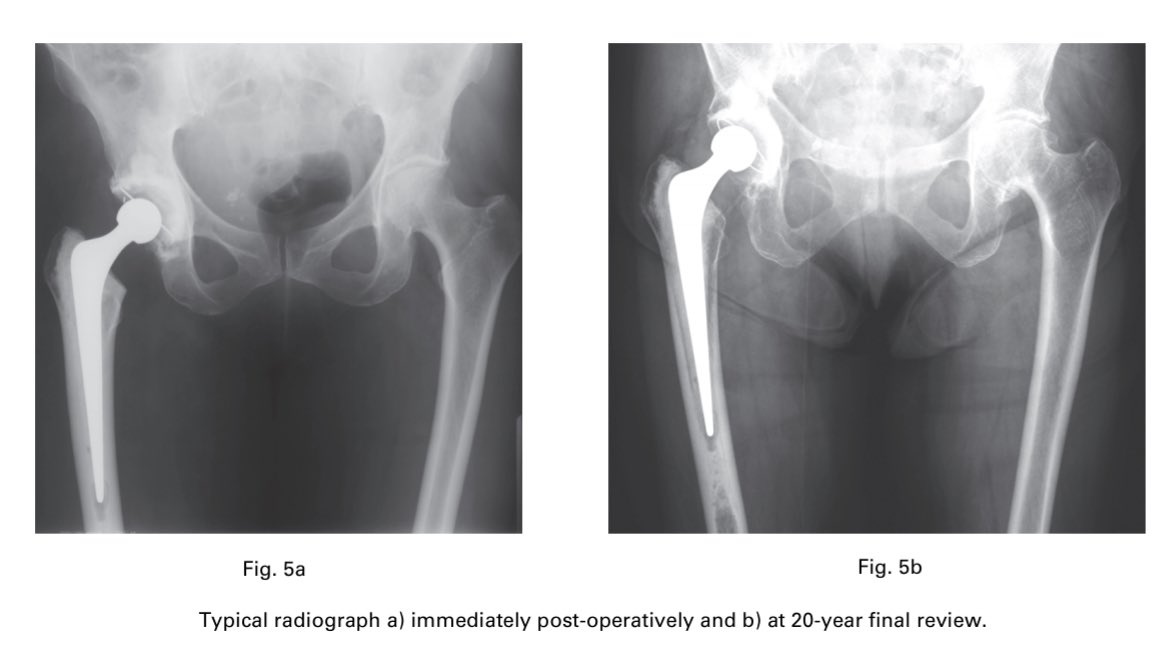

Mainly posterior approach (Exeter was designed for the posterior approach but can be used in any approach). Old cups and poly, all cemented in this series. Note the small head sizes at that time.

Look at previous tweets for why the femur is preserved. More to come in the next few weeks. Not a bad looking femur at 20 years post-op. #orthotwitter #ExeterHip50